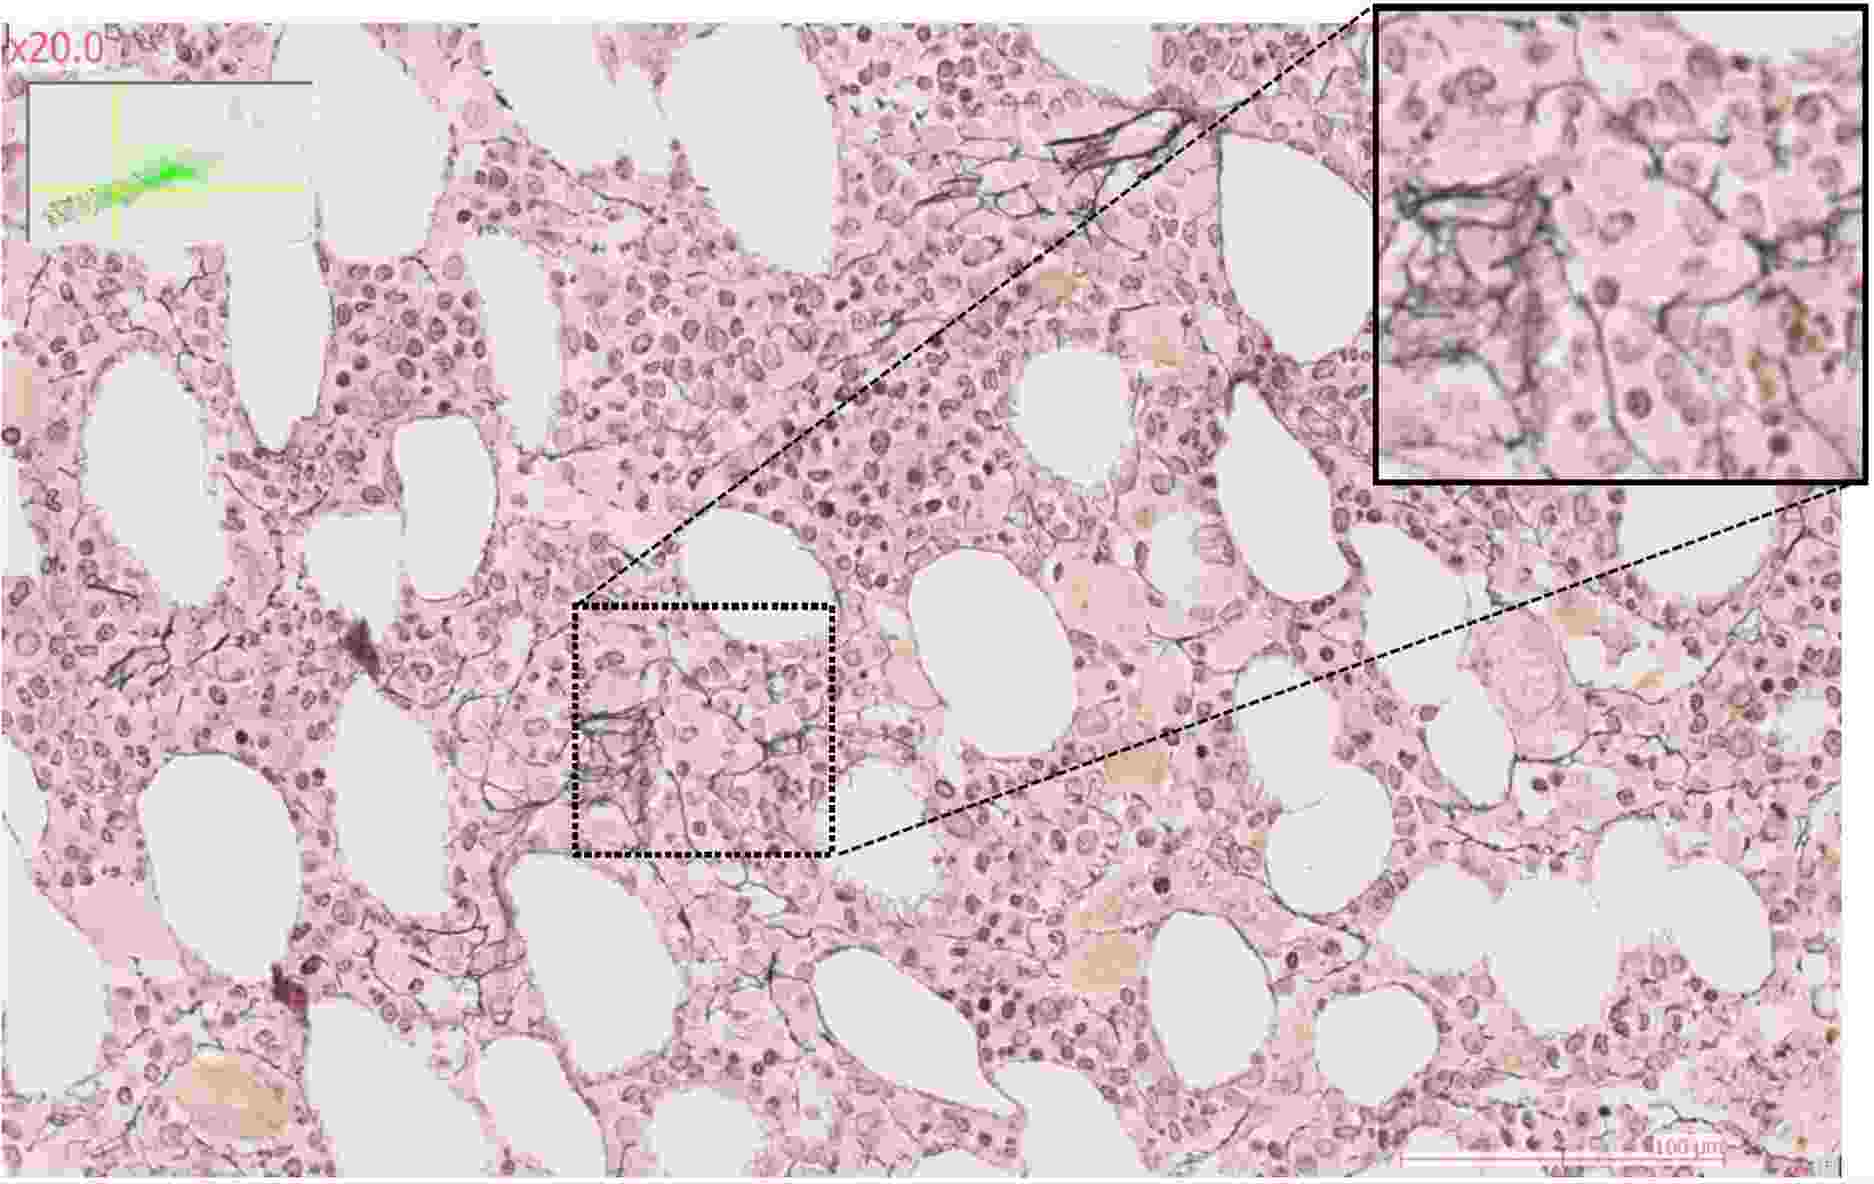

Ces altérations sont reflétées par des changements de programmes d’expression génique au niveau des cellules souches à l’apex de la pathologie, dont la conséquence est une perte de contrôle de l’homéostasie hématopoïétique. Cette perte de contrôle passe par des changements de l’organisation spatiale de la moelle osseuse chez les patients atteints de SMP ou SMD, dont certains évoluent en LAM.

L’utilisation de technologies d’imagerie sans marquage, telles que l’imagerie de phase quantitative ou la mesure d’anisotropie (Phasics), nous permet de générer des données quantitatives d’un genre nouveau afin d’évaluer le contenu en os trabéculaire et en fibre de collagène du microenvironnement médullaire.

Afin d’étudier les modifications du stroma en condition pathologique, l’équipe s’appuie sur des modèles de leucémies aigües myéloïdes chez la souris en se focalisant sur les étapes initiales de la leucémogénèse (envahissement de la moelle osseuse inférieure à 20%). Ces modèles murins permettent de suivre la progression leucémique grâce à différentes techniques telles que la cytométrie en flux spectrale, ou d’imagerie comme le RNA-scope ou la microscopie confocale.